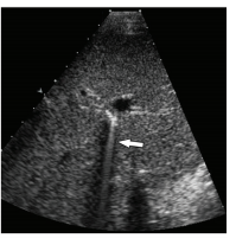

An artifact in this image is caused secondary to what property of the ultrasound waves?

attenuation

Shadowing artifact occurs secondary to the reflective and attentive properties of the imaged structure. As seen in this example, the gall bladder stone is highly attenuating and reflectiv3e leading to complete abscence of sound waves behind the stone.